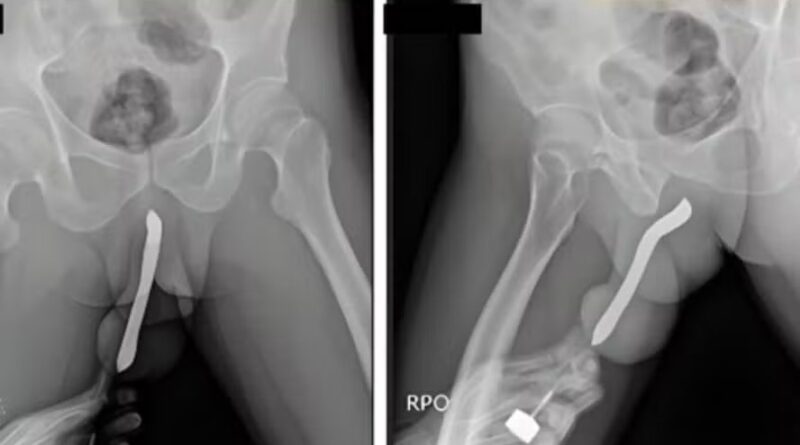

Um grande número de pessoas procura prontos-socorros todos os anos após introduzir objetos nos órgãos genitais. A partir desse cenário, o site norte-americano Defector analisou dados recentes da Comissão de Segurança de Produtos de Consumo dos Estados Unidos (CPSC), que reúne registros de atendimentos de emergência e os motivos que levam pacientes ao hospital.